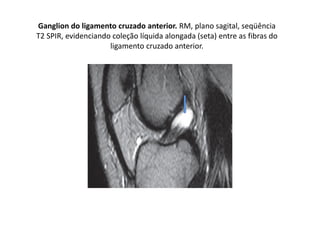

Posicionamento do ligamento cruzado anterior

Ganglion do ligamento cruzado anterior. RM, plano sagital, seqüência

T2 SPIR, evidenciando coleção líquida alongada (seta) entre as fibras do

ligamento cruzado anterior.